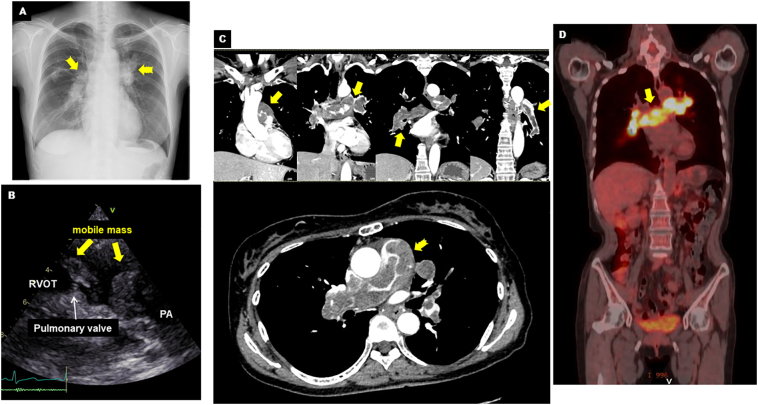

On admission, her blood pressure was 100/60 mmHg and heart rate was 90 bpm with sinus rhythm. D-dimer and brain natriuretic peptide (BNP) levels were slightly elevated (D-dimer = 4.3 μg/ml; reference <1.0 μg/ml and BNP = 62.5 pg/ml; reference ≤18.4 pg/ml). Chest X-ray showed dilated central pulmonary arteries, suggesting pulmonary hypertension (Fig. 1A, yellow arrows). A large mass that moved back and forth across the pulmonary valve was found by echocardiography (Fig. 1B, Online Video 1). A color Doppler ultrasound detected moderate tricuspid regurgitation with a pressure gradient of 88 mmHg, which confirmed the presence of pulmonary hypertension. Contrast-enhanced CT revealed filling defects occupying in the main pulmonary trunk extending to bilateral pulmonary arteries (Fig. 1C, yellow arrows). There was no sign of metastatic tumors originating from other organs. Suspecting a pulmonary artery tumor, 18F-fluorodeoxyglucose (FDG)-PET/CT was performed to rule out PE. Intense FDG-uptake was observed in the pulmonary arteries, particularly at the main pulmonary trunk. This finding strongly suggested pulmonary artery tumor (Fig. 1D, yellow arrow). There was a high maximum standardized uptake (max SUV) of 13.2. The red color-coded region of iodine map (Fig. 2B) using dual-energy CT (Fig. 2A) was a near match for the PET image of the FDG-uptake region (Fig. 2C). The detailed protocol for CT analysis and its validation in other cases are described in the Online materials.

Fig. 1.

Multi-modality imaging of pulmonary artery intimal sarcoma. (A) Chest X-ray showing dilated central pulmonary arteries (yellow arrows). (B) Echocardiography demonstrating mobile mass adjacent to the pulmonary valve between RVOT and PA. (C) Contrast-enhanced CT demonstrating the filling defects in main pulmonary trunk expanding to bilateral pulmonary arteries (yellow arrows). (D) FDG-PET/CT showing the intense FDG uptakes (yellow arrow).

CT, computed tomography; FDG, 18fluoro-2-deoxyglucose; PA, pulmonary artery; PET, positron emission tomography; RVOT, right ventricular outflow tract.